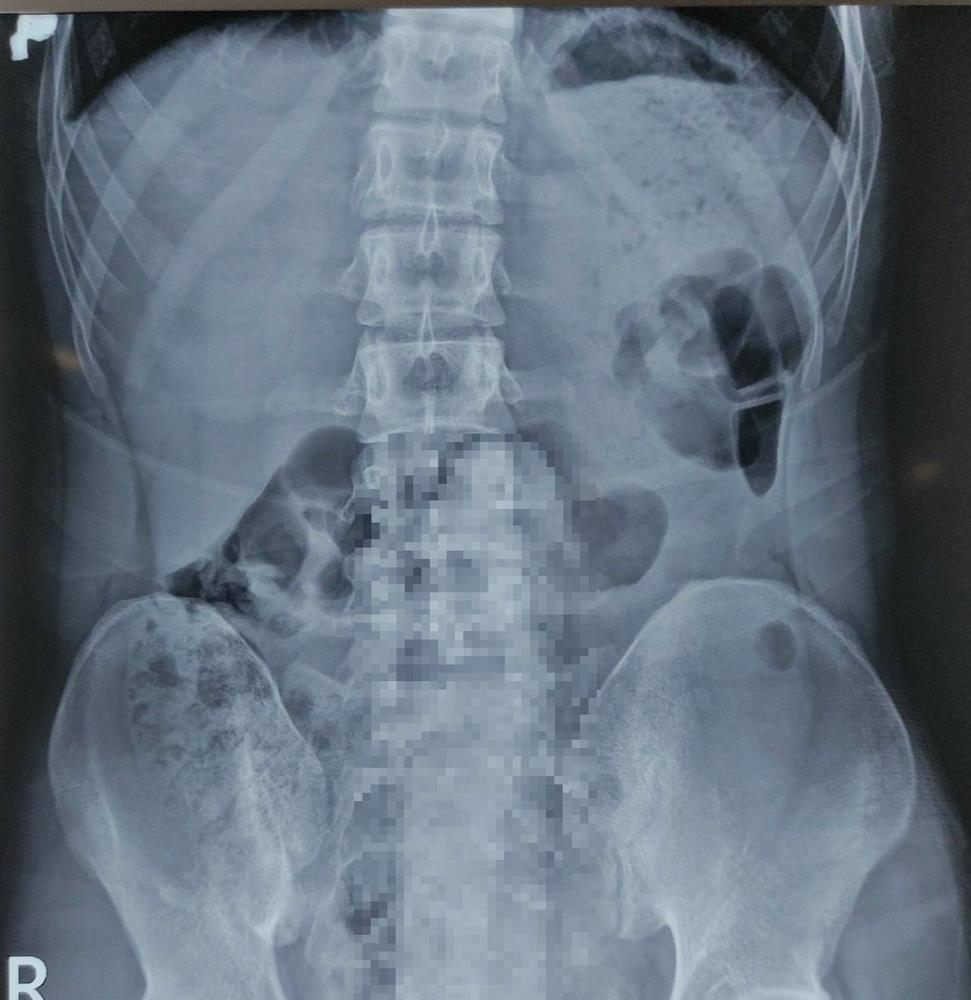

Bệnh nhân được đưa đến Khoa Cấp cứu, Bệnh viện Quân y 175. Qua thăm khám và chụp X-quang, bác sĩ phát hiện có dị vật hình dạng giống “dương vật” nằm sâu trong trực tràng. Do đó, bệnh nhân được chuyển lên Khoa Phẫu thuật - Gây mê hồi sức để tiến hành lấy dị vật.

Hình ảnh Xquang cho thấy có dị vật (phần được làm mờ) trong trực tràng của bệnh nhân. Ảnh: BVCC.